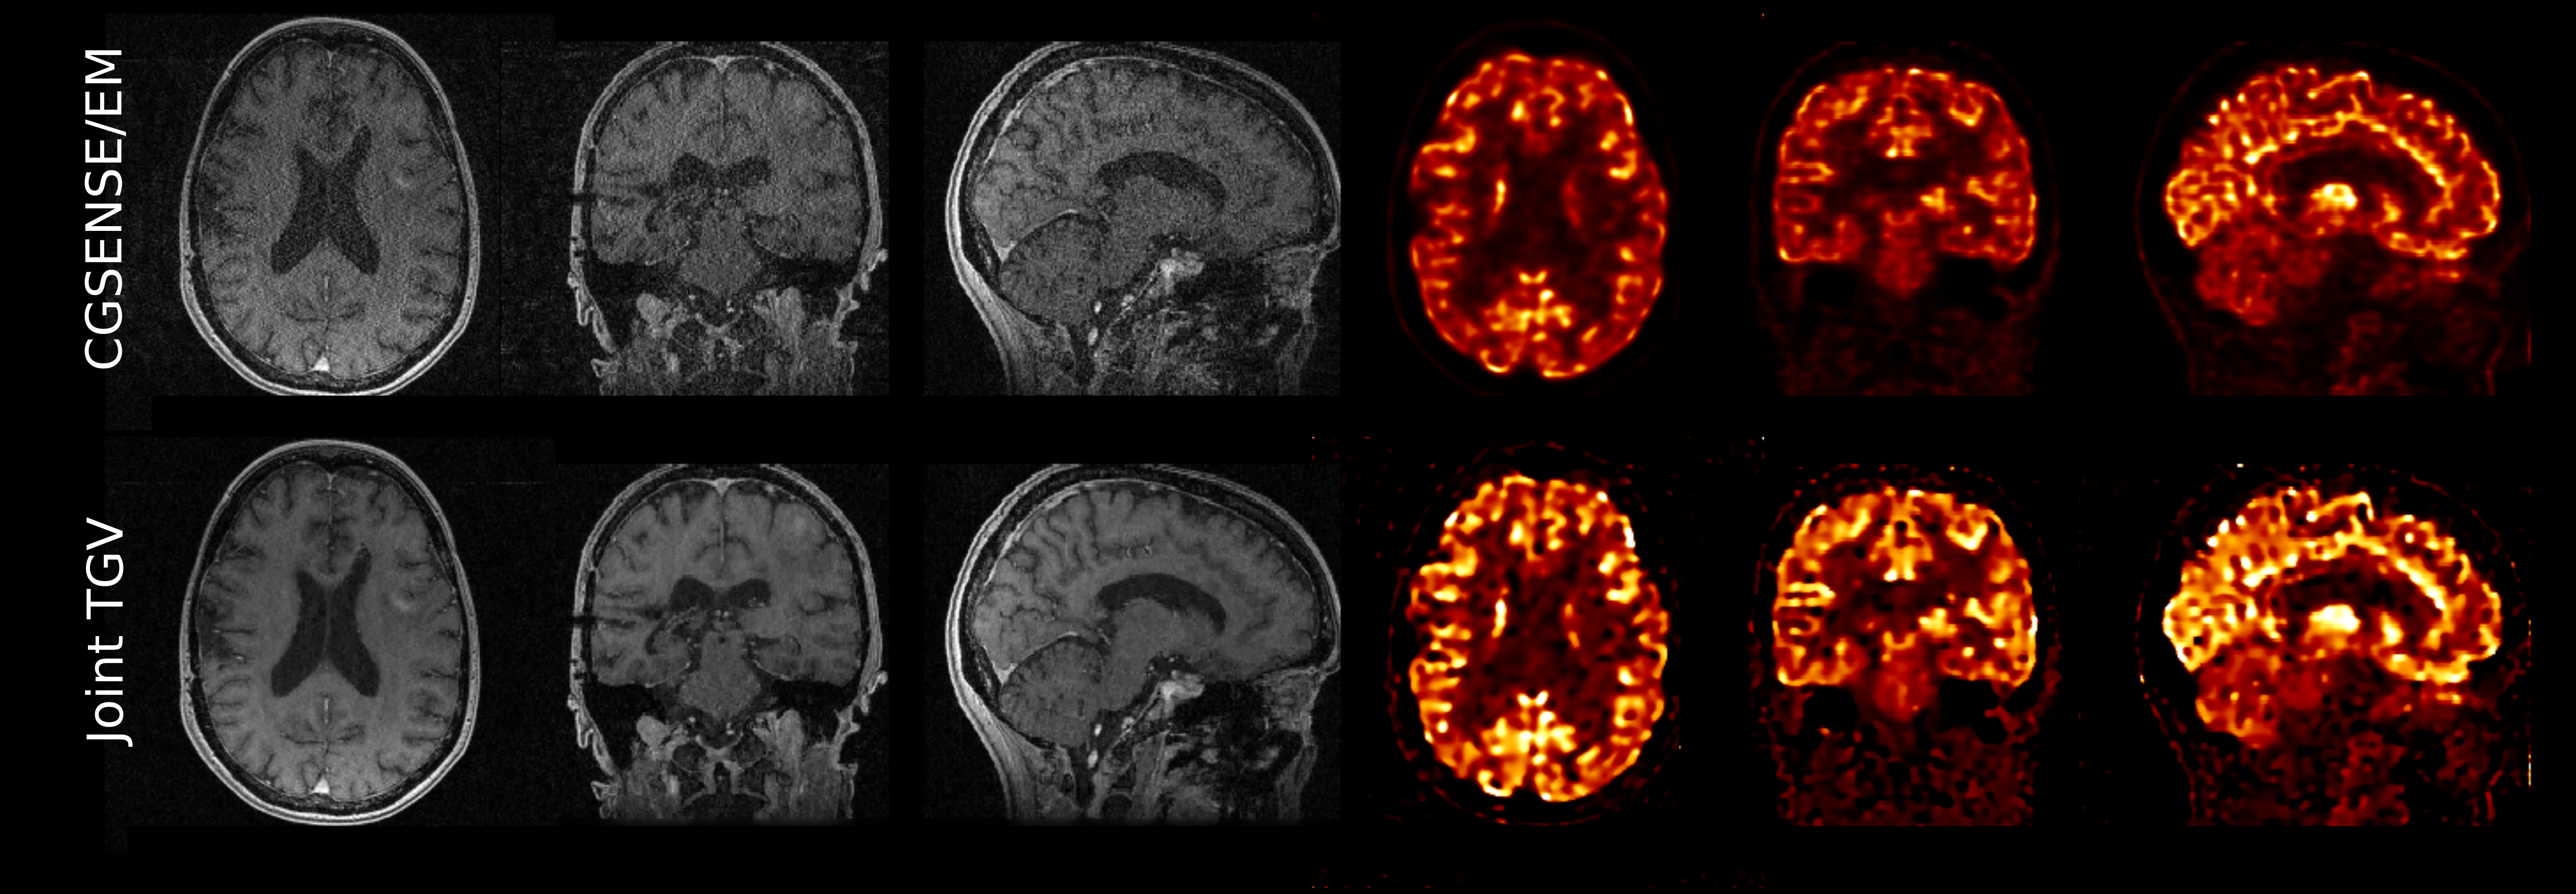

• [46] K. Vunckx, A. Atre, K. Baete, A. Reilhac, C.M. Deroose, K. Van Laere, and J. Nuyts, Evaluation of three MRI-based anatomical priors for quantitative PET brain imaging., IEEE Trans. Med. Imag. 31 (2012), no. 3, 599–612.